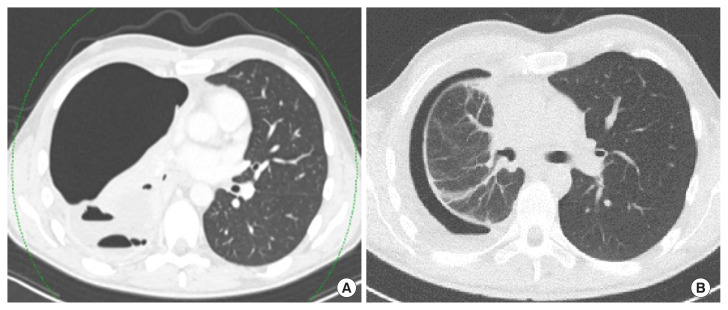

约3%至5%的间变性淋巴瘤激酶(ALK)基因发生致癌重排的个体发展为非小细胞肺癌(NSCLC)。Brigatinib是一种有效的下一代ALK酪氨酸激酶抑制剂(TKI),已显示出显着的全身和颅内反应,以及改善的无进展生存期,具有可接受的安全性。根据欧洲肿瘤医学学会指南,ALK易位和性能状态为0-3的患者可以接受TKI(布加替尼、阿勒替尼或氯拉替尼)一线治疗。据我们所知,这是第一例布加替尼增加剂量后肺部出现囊性或大泡性变化的报道。在这里,我们描述了一个37岁的男性,从不吸烟,在接受布加替尼治疗肺内转移的非小细胞肺癌时,肺实质出现渐进性弥漫性囊性改变。临床医生应该对这种潜在的非典型肺不良反应保持警惕,包括肺实质囊性或大泡性转化的可能性。

Approximately 3% to 5% of individuals with oncogenic rearrangements in the anaplastic lymphoma kinase (ALK) gene develop non-small cell lung cancer (NSCLC). Brigatinib, a potent next-generation ALK tyrosine kinase inhibitor (TKI), has demonstrated significant systemic and intracranial responses, as well as improved progression-free survival, with an acceptable safety profile. According to European Society for Medical Oncology guidelines patients with ALK translocation and performance status 0-3 can be offered 1st line treatment with TKI (brigatinib, alectinib, or lorlatinib). To our knowledge, this is the first reported case of cystic or bullous changes in the lungs following incremental dosing of brigatinib. Here, we describe a 37-year-old male, a never-smoker, who developed progressively diffuse cystic changes in the lung parenchyma while receiving brigatinib treatment for NSCLC with intrapulmonary metastases. Clinicians should remain vigilant for this potential atypical pulmonary adverse effect, including the possibility of cystic or bullous transformations in the lung parenchyma.